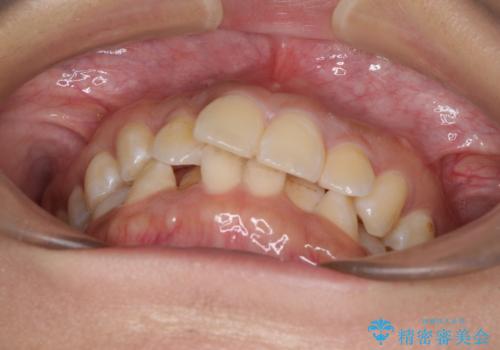

前歯のデコボコと隠れてしまう下顎前歯 インビザラインですっきりと改善

- 前歯のデコボコと、深い咬み合わせにより前歯が隠れていることを気にして来院された患者様です。

海外に長期滞在する予定があるとのことで、インビザラインにて矯正治療を行うこととしました。